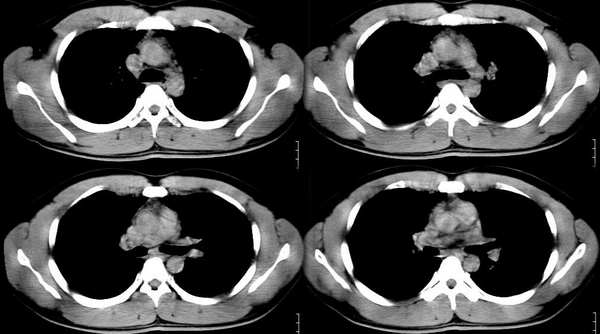

以下是引用ssl1_1在2006-3-2 22:37:00的发言:[br]肺泡蛋白沉积症(外围型)

以下是引用huangaiying1在2006-3-3 16:03:00的发言:[br]双肺弥漫分布的磨玻璃影及小结节影,以双上肺为著,纵隔内未见明显增大的淋巴结影,结合病史,考虑过敏性肺炎

以下是引用guandong在2006-3-4 20:57:00的发言:[br]两肺弥漫分布磨玻璃影,以中外带为主,可见于过敏性肺炎、肺泡蛋白沉着症、农民肺等,但不支持结核。